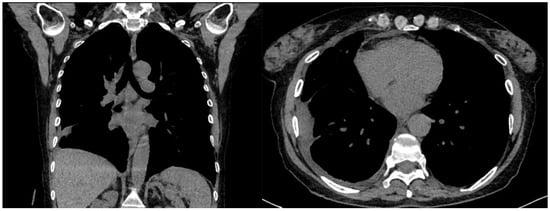

A 61-year-old female patient with obesity, discoid lupus, bipolar disorder, arterial hypertension, and hypothyroidism was admitted to our Respiratory Unit for respiratory failure and evidence of a large complex PEff on her chest CT, which also revealed complete atelectasis of the right lower lobe (RLL) and almost-complete atelectasis of the middle lobe (ML) and right upper lobe (RUL) (Figure 6). There was also a solid tissue surrounding the right main bronchus and its main branches, which was suspected to be neoplastic. It had a central hypodense area consistent with necrosis.

Peripheral enhancement of the pleural layers was also observed.

A chest drain was placed, with the collection of purulent fluid. High-flow oxygen therapy was initiated, and the patient was treated with broad-spectrum antibiotics (vancomycin + piperacillin/tazobactam). The fluid was analyzed and was positive for Streptococcus intermedius and showed typical chemical and physical characteristics of exudates, so a diagnosis of a right pleural empyema was made. As a result, 3 days of treatment with intrapleural urokinase was initiated. The urokinase was administered in a daily single dose of 100,000 UI diluted in 50 mL of saline solution. At the end of the IPFT, a chest US was performed. It showed a decrease in effusion with a single loculation that extended over a width of three intercostal spaces. A chest CT was also performed, which confirmed the decrease in PEff and showed the re-expansion of RUL and ML and the partial re-expansion of RLL. The increased density formation described earlier was no longer evident. The patient was then referred for uniportal VATS to complete the toilette and obtain biopsies. Multiple pleural biopsies were performed. The results were consistent with chronic pleuritis, and no elements were noted that were suspicious in terms of malignancy. The biopsy showed fibrous tissue with hemosiderin-laden macrophages and scattered inflammatory cells. No neoplastic cells could be observed. Thus, a malignant lesion could be excluded. The chest tube was later removed, a chest CT was performed, and the patient was finally discharged (Figure 7).

Figure 6. Chest CT scan of the mediastinal window in the coronal (A) and axial (B) plane, showing a large right pleural effusion, occupying almost the entire hemithorax with organized appearance. There is also a complete right lower lobe atelectasis and almost-complete right middle and upper lobe atelectasis with sparing of anterior sectors.